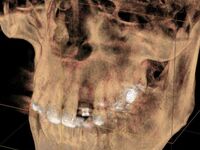

Bei nicht oder nicht vollständig durchgebrochenen Weisheitszähnen wird die darüber liegende Schleimhaut beiseite geschoben und der darüber liegende Knochen entfernt. Dann wird der Zahn mit einem Hebel entfernt. Ist dies aus anatomischen Gründen nicht im Ganzen möglich, wird das Durchtrennen des Zahnes notwendig. Das Trennen des Zahns ist obligat wenn die Platzverhältnisse keine andere Entfernungsmethode zulassen oder sich die Zahnwurzeln in unmittelbarer Nervnähe befinden. Die Wunde kann vernäht oder offen gelassen werden. Um Folgeschäden wie eine Taubheit der Unterlippe zu vermeiden kann präoperativ ein 3D DVT ( DIGITALES VOLUMENTOMOGRAMM ) zur Abklärung der Lagebeziehung von Wurzeln und Nerv sowie zur OP-Planung angefertigt werden.

Zu einer Wurzelspitzen-Entfernung wird Ihr Zahnarzt oder Kieferchirurg dann raten, wenn ein chronisch entzündlicher Prozess durch eine Wurzelbehandlung nicht behoben werden kann oder eine konventionelle Wurzelbehandlung nicht möglich ist. Auch wenn sich im Röntgenbild Veränderungen im Bereich der Wurzelspitze zeigen, die nicht eindeutig zuzuordnen sind, kann eine Wurzelspitzen-Resektion empfehlenswert sein. Um die Region der Wurzelspitzen genauer abzubilden ist es präoperativ möglich, durch ein 3D DVT (DIGITALES VOLUMENTOMOGRAMM) die Region dreidimensional abzubilden, um so eine bessere OP-Planung zu erhalten oder sich über die Frage der Erhaltungswürdigkeit des Zahns klar zu werden.

Solch ein Vorgehen erfordert allerdings auch eine möglichst exakte Diagnostik, die bei uns in der Regel dreidimensional mittels DVT erfolgt. So kann die Implantation vorher am Rechner dreidimensional simuliert werden, bevor sie am Patienten durchgeführt wird.